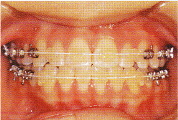

○セラミックタイプのブラケット(透明な装置)

目立たない透明な装置です。